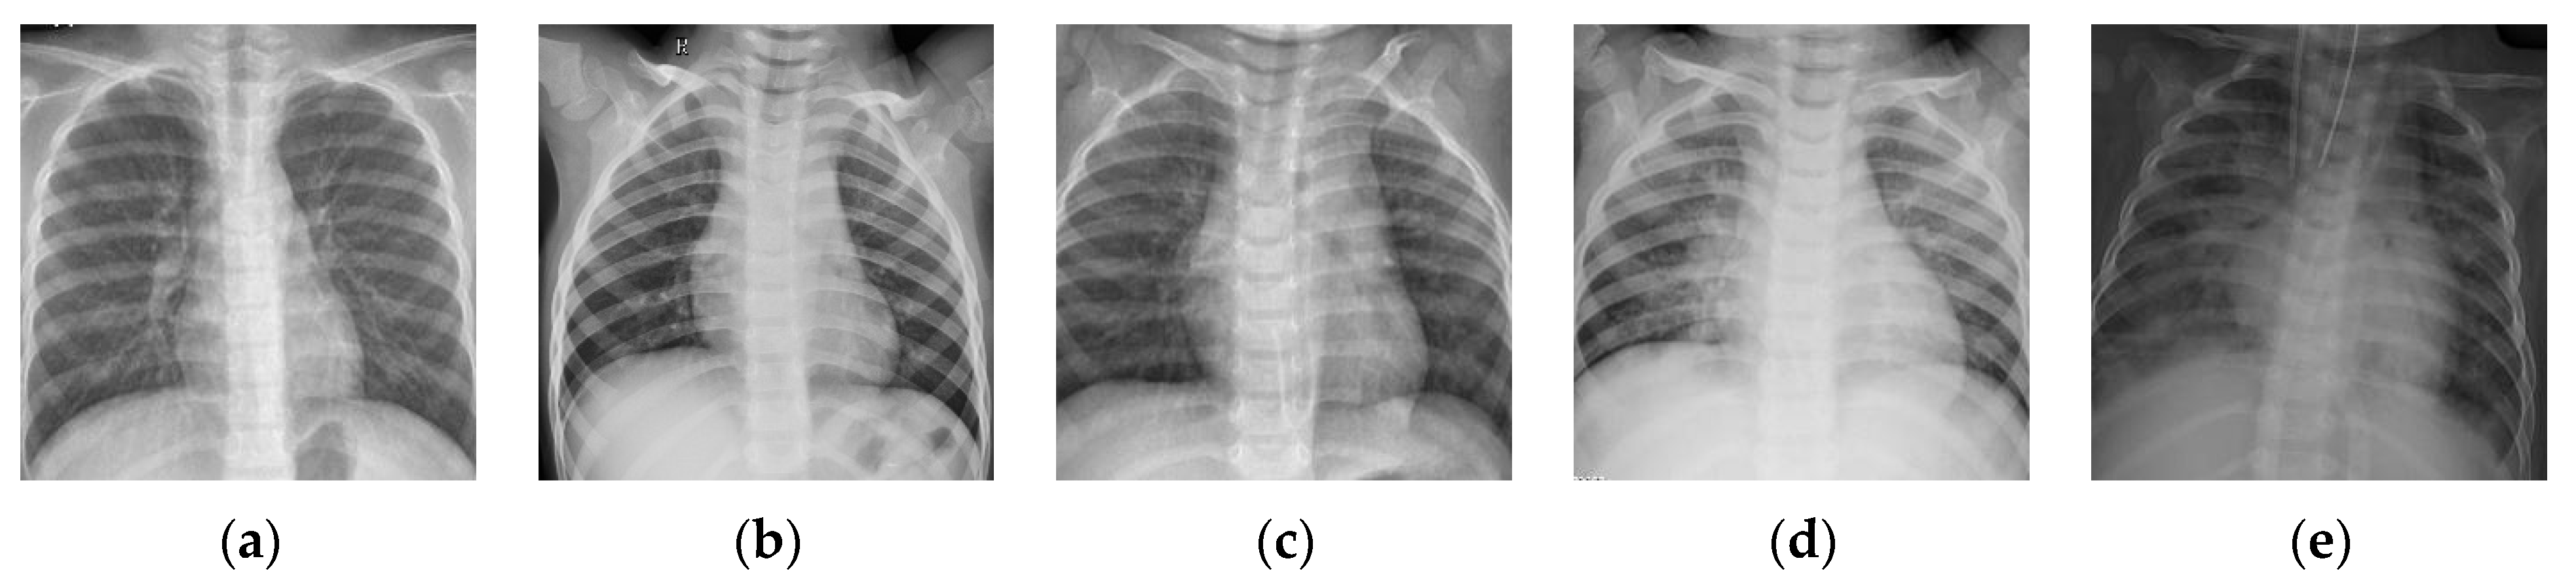

Figure 10.

Examples of the dataset Chest-2. (a–c) Normal; (d,e) pneumonia.

To further verify the consistency of the proposed BSTriplet loss, we have carried out comparative experiments on another dataset of chest X-ray images denoted as “Chest-2”. This dataset is also downloaded from the Kaggle [43] website. Here, Chest-2 is used for the classification of lung images into normal lung images and pneumonia images. Some examples are shown in Figure 10. The construction of Chest-2 is listed in Table 5. Each of the mentioned four light-weighted networks is trained with four kinds of losses on Chest-2. Similar to the experiments on Chest-1, all these images in Chest-2 are resized into . We have performed the K-means algorithm to partition the training images into six groups, and randomly selected six samples from each group to build the input batch for the proposed CE+BST loss.